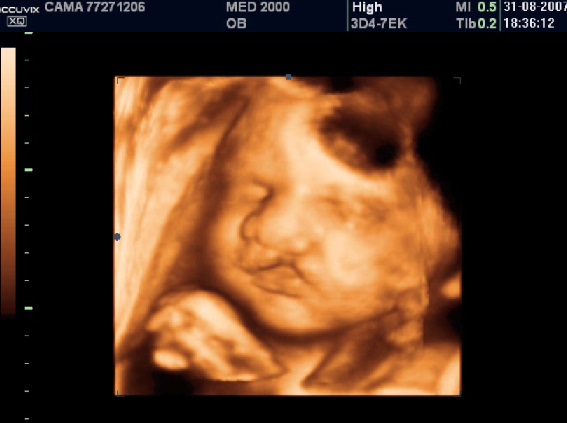

La Diagnosi Prenatale si basa su:

-         anomalie facciali unilaterali (asimmetria, anoftalmia  e microftalmo unilaterali).